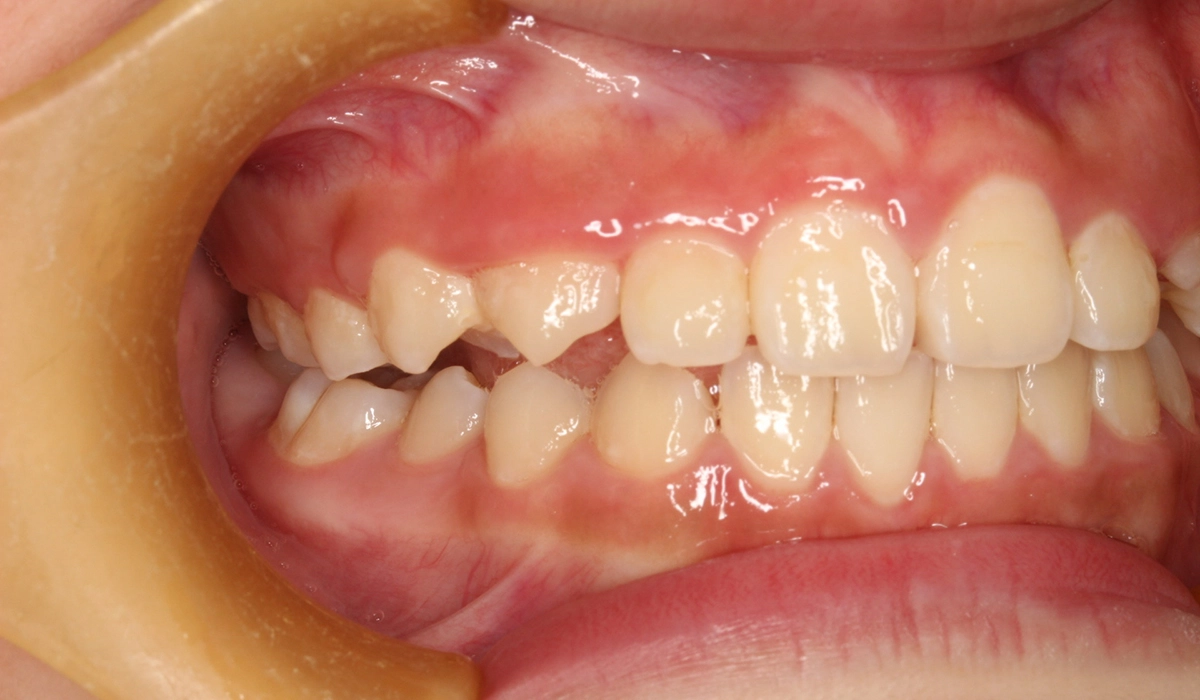

術前:左側